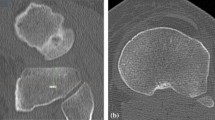

Surgical technique

A posterior stabilised total knee replacement with a fixed insert (P.F.C. Sigma; DePuy Orthopaedics, Inc; Warsaw, IN, USA) was implanted with cement in all patients. Femoral intramedullary and tibial extramedullary alignment guides were used for implantation. The first step of the implantation process was preparation of the tibia [14]. The tibial guide was aligned with the sulcus between the tibial spines and the middle of the posterior cruciate ligament at the knee and with the tibialis anterior tendon at the ankle, which created neutral coronal alignment (Fig. 1a, b). The tibial cut was made so that 8–10 mm of bone was removed from the lateral tibial plateau. The tibia was sized based on the AP dimension of the lateral tibial plateau, by selecting the size that best covered the lateral plateau without overhang. The tibial component was centred on the lateral plateau and externally rotated until the middle of the component was aligned with the AP between the tibial spines and the middle of the posterior cruciate ligament. On the femoral side, the rotational alignment was approximated using 3° of external rotation from the posterior condylar axis.

The reference points used for tibial guide placement. a The preferred reference points for tibial component placement were the sulcus between the tibial spines (star) and the middle of the posterior cruciate ligament (triangle) at the knee and the tibialis anterior tendon (arrow) at the ankle. b After placement of the tibial guide according to the reference points